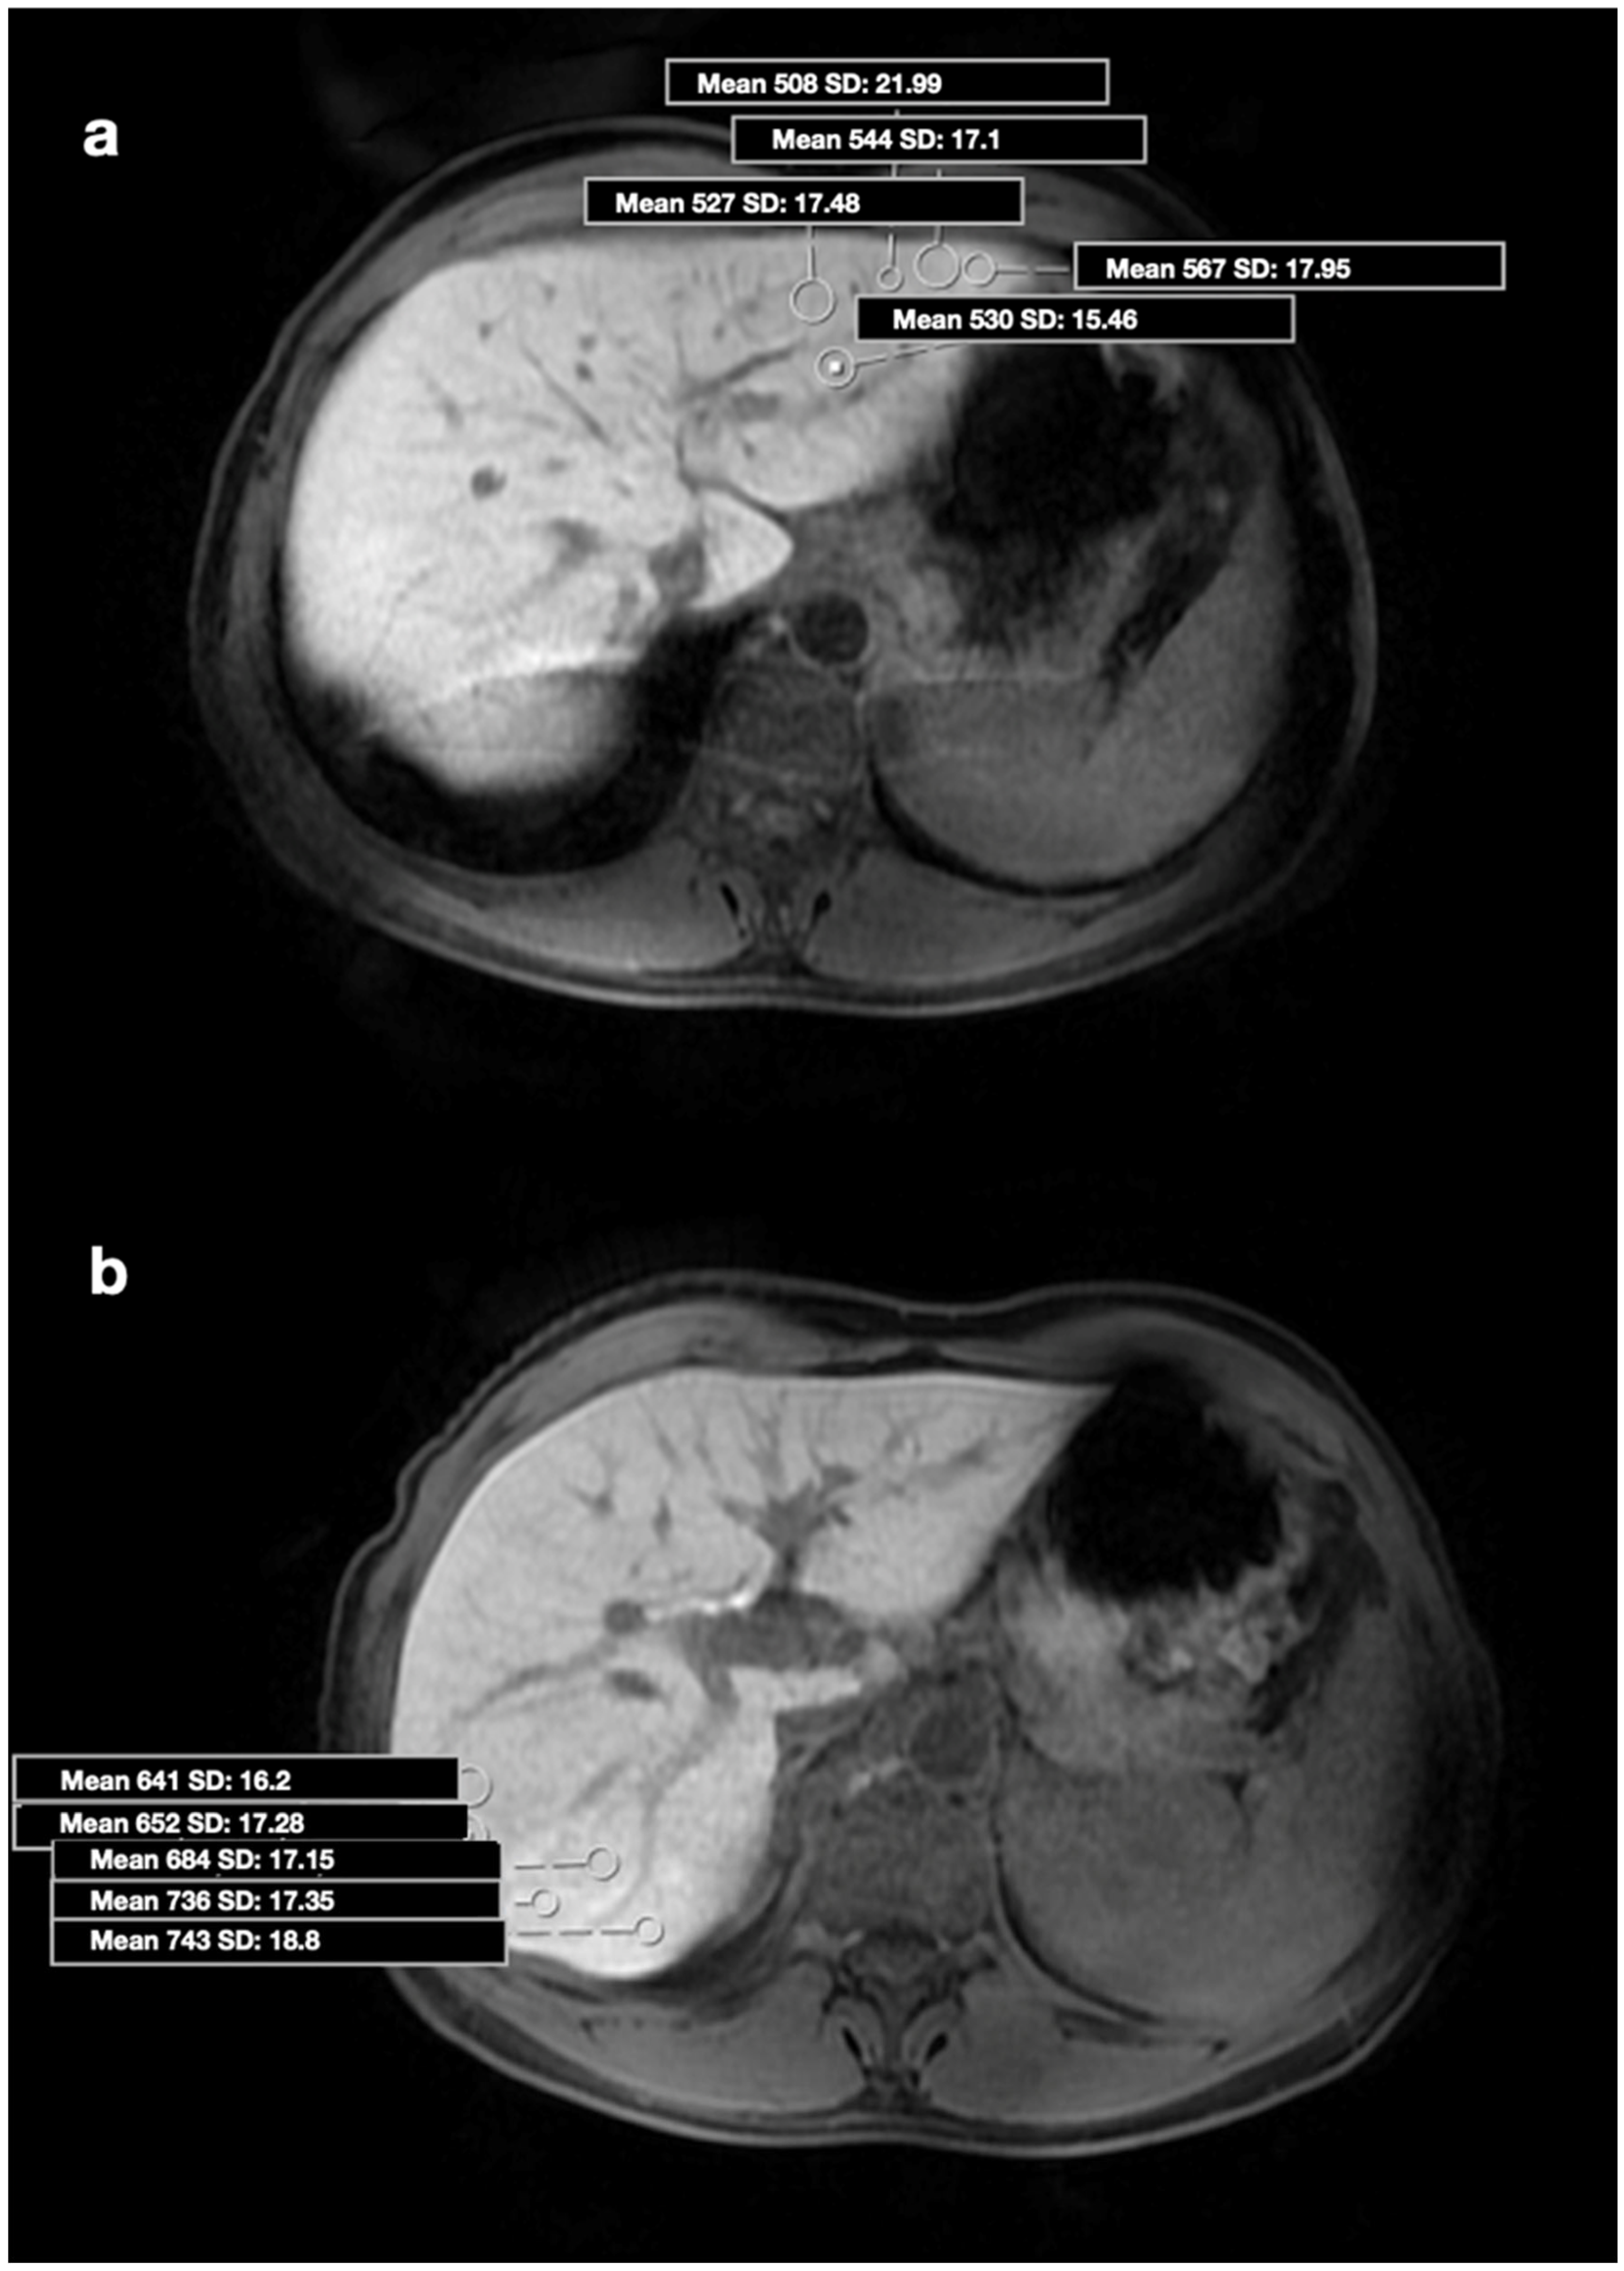

2.2. Image Analysis and Biopsy Procedure

| SI, mean (range) | 710.1 ± 231.9 (323–1592) | 573.2 ± 175.4 (161–1095) | 0.004 |

| SI, mean | 489.5 ± 100.6 | 793.8 ± 191.1 | <0.001 |